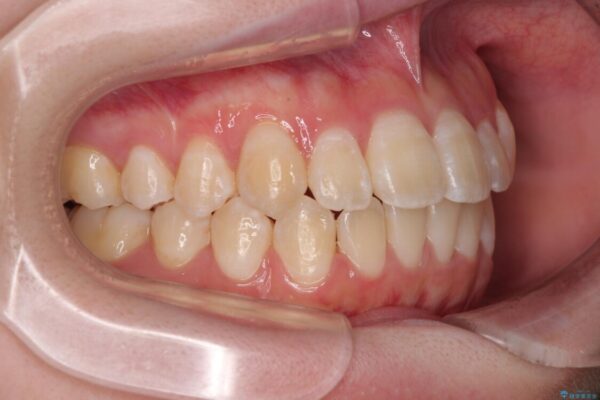

「前歯のデコボコ(叢生)をきれいに整えたい」とのことでご来院されました。

治療前

• 【モニター】前歯のデコボコをスッキリ解消!目立ちにくいワイヤー矯正でスピーディに治療完了 治療前画像